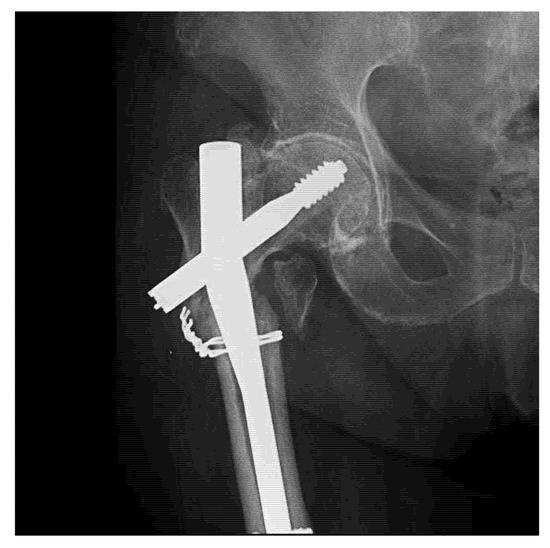

For intramedullary nails, it is well-recognized that the failure process is usually initiated in the locking holes, proximally or distally (case presented in Figure 6). Sliding screw hip plates are prone to significant wear and corrosion due to moving components [37,38]. For plates, the breakdown starting point is commonly situated around the holes where the cross-sectional area is reduced and where interaction with the screw heads generates wear and corrosion fatigue under localized stress concentration [39].

Figure 6.

Radiography of a clinical case with failure of a Gamma Nail—72-year-old female patient.